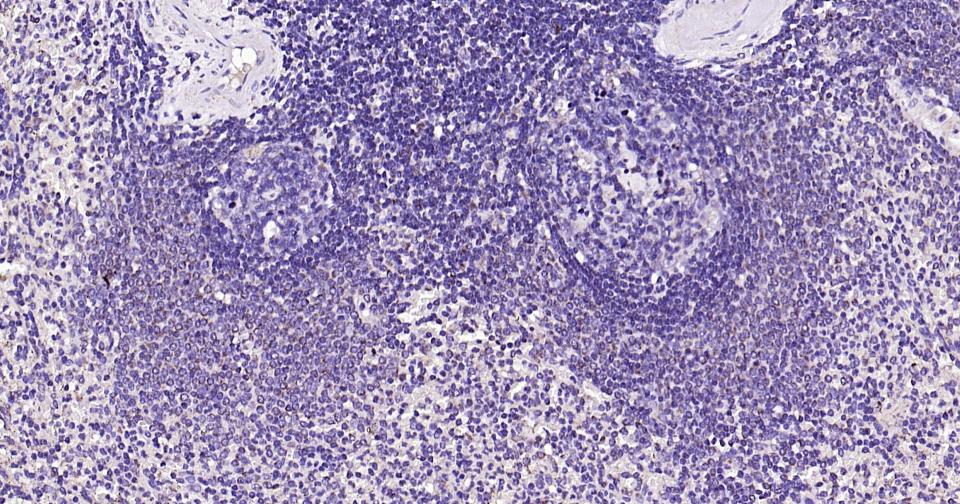

Paraformaldehyde-fixed, paraffin embedded Human Spleen; Antigen retrieval by boiling in sodium citrate buffer (pH6.0) for 15 min; Antibody incubation with Bak Monoclonal Antibody, Unconjugated(bsm-61174R) at 1:200 overnight at 4°C, followed by conjugation to the SP Kit (Rabbit, SP-0023) and DAB (C-0010) staining.